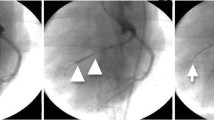

From baseline to follow-up scans, CTP-MBF presented a stepwise increase in the infarcted myocardium (68.51 ± 11.04 vs. 86.73 ± 13.32 vs. 109.53 ± 26.64 ml/100 ml/min, p = 0.001) and the penumbra (104.92 ± 29.29 vs. 120.32 ± 24.74 vs. 183.01 ± 57.98 ml/100 ml/min, p = 0.008), but not in the remote myocardium (150.05 ± 35.70 vs. 166.66 ± 38.17 vs. 195.36 ± 49.64 ml/100 ml/min, p = 0.120). The CTP-MBF correlated with max slope (r = 0.584, p < 0.001), max signal intensity (r = 0.357, p < 0.001), and time to max (r = − 0.378, p < 0.001) by CMR perfusion. Moreover, CTP-MBF defined the infarcted myocardium on triphenyl tetrazolium chloride staining (AUC: 0.810, p < 0.001) and correlated with microvascular density on CD31 staining (r = 0.561, p = 0.002).

Tanabe Y, Kido T, Uetani T et al (2016) Differentiation of myocardial ischemia and infarction assessed by dynamic computed tomography perfusion imaging and comparison with cardiac magnetic resonance and single-photon emission computed tomography. Eur Radiol 26(11):3790–3801

Bamberg F, Marcus RP, Becker A et al (2014) Dynamic myocardial CT perfusion imaging for evaluation of myocardial ischemia as determined by MR imaging. JACC Cardiovasc Imaging 7(3):267–277